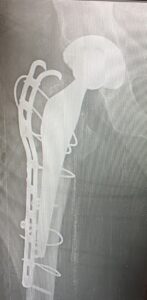

- Περιπροθετικό κάταγμα. Κάταγμα του οστού σε γειτνίαση με ορθοπεδικό εμφύτευμα. Διακρίνεται το κάταγμα κάτωθεν του εμφυτεύματος.

- Περιπροθετικό κάταγμα ανάμεσα σε δύο εμφυτεύματα με αστοχία της πλάκας οστεοσύνθεσης.